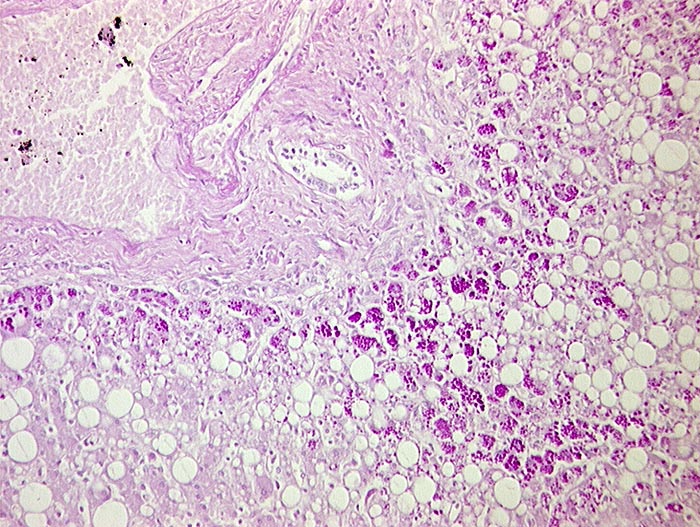

AP/ Leber bei alpha-1-Antitrypsinmangel

Leber bei alpha-1-Antitrypsinmangel